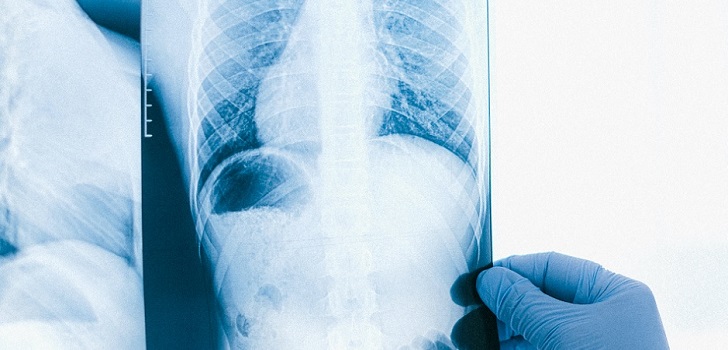

Unilabs estrecha la mano con Qure.ai. El proveedor de servicios de diagnóstico ha anunciado una asociación con Qure.ai, grupo especializado en soluciones de inteligencia artificial (IA) médica. A través de esta asociación, Unilabs desplegará la solución de IA de Qure.ai para ayudar en la clasificación de las radiografías de tórax en exámenes normales y anormales. No ha trascendido cantidad económica fruto de la operación.

La solución se implementará inicialmente y se pondrá a prueba en la rama de servicios electivos de Reino Unido de Unilabs TMC para ayudar a aumentar la capacidad y optimizar el flujo de trabajo de radiología, según señala la compañía de servicios de diagnóstico en un comunicado.

La solución para radiografías de tórax de Qure.ai, qXR, con certificación CE, ayudará a identificar qué casos no tienen hallazgos clínicamente relevantes, permitiendo a los radiólogos detectarlos incluso antes de abrir el caso. Aproximadamente, el 50% de las radiografías de tórax no son destacables y deben completarse rápidamente para que los radiólogos puedan liberar capacidad y centrar su atención en aquellos exámenes que tienen hallazgos relevantes.

El software de radiografía de tórax de Qure.ai puede detectar múltiples anomalías pulmonares en menos de un minuto. Puede evaluar con precisión los hallazgos radiológicos que sugieren una serie de enfermedades pulmonares, como la neumonía, la Epoc, la tuberculosis y la insuficiencia cardíaca, entre otras.

“Este es otro hito importante del Centro de Excelencia de IA de Unilabs y un testimonio de nuestros esfuerzos para seguir implementando soluciones de IA y preparar nuestro negocio de radiología para el futuro”, explica Christian Rebhan, director médico y de operaciones de Unilabs. “La solución de rayos X de tórax con IA de Qure.ai nos ayudará a clasificar los casos entrantes, reduciendo el tiempo de lectura de las radiografías de tórax no notables entre un 25% y un 50%”, añade.